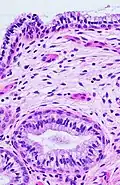

The endocervical mucosa is about 3 mm (0.12 in) thick and lined with a single layer of columnar mucous cells. It contains numerous tubular mucous glands, which empty viscous alkaline mucus into the lumen.[4] In contrast, the ectocervix is covered with nonkeratinized stratified squamous epithelium,[4] which resembles the squamous epithelium lining the vagina.[17]: 41 The junction between these two types of epithelia is called the squamocolumnar junction.[17]: 408–11 Underlying both types of epithelium is a tough layer of collagen.[18] The mucosa of the endocervix is not shed during menstruation. The cervix has more fibrous tissue, including collagen and elastin, than the rest of the uterus.[4]

The squamocolumnar junction of the cervix, with abrupt transition: The ectocervix, with its stratified squamous epithelium, is visible on the left. Simple columnar epithelium, typical of the endocervix, is visible on the right. A layer of connective tissue is visible under both types of epithelium. -